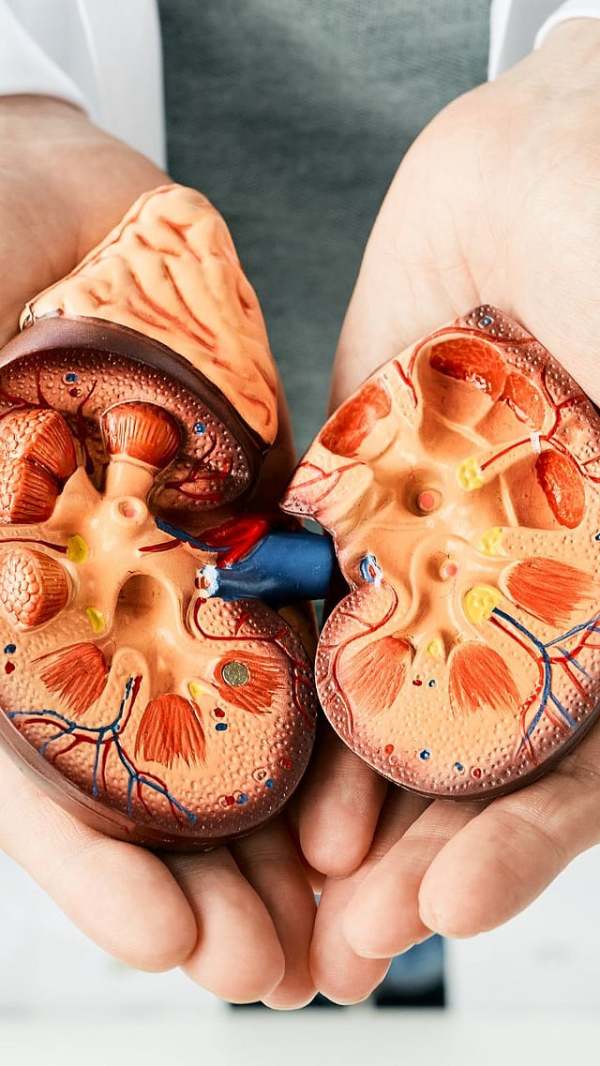

किडनीवर येतो ताणवारंवार लघवी रोखल्यामुळे मूत्रपिंडावर (Kidney) अतिरिक्त दाब निर्माण होतो, ज्यामुळे किडनी निकामी होण्याचा धोका वाढतो.

मुतखड्याची समस्यालघवीमध्ये युरिक ॲसिड आणि कॅल्शियम ऑक्सालेटसारखे घटक असतात. लघवी रोखल्यामुळे हे घटक जमा होऊन मुतखडा तयार होण्याची शक्यता वाढते.

मूत्राशयाचे स्नायूसतत लघवी रोखून ठेवल्याने मूत्राशय ताणले जाते. यामुळे कालांतराने मूत्राशयाचे स्नायू सैल आणि कमकुवत होतात, ज्यामुळे लघवीवर नियंत्रण राहत नाही.